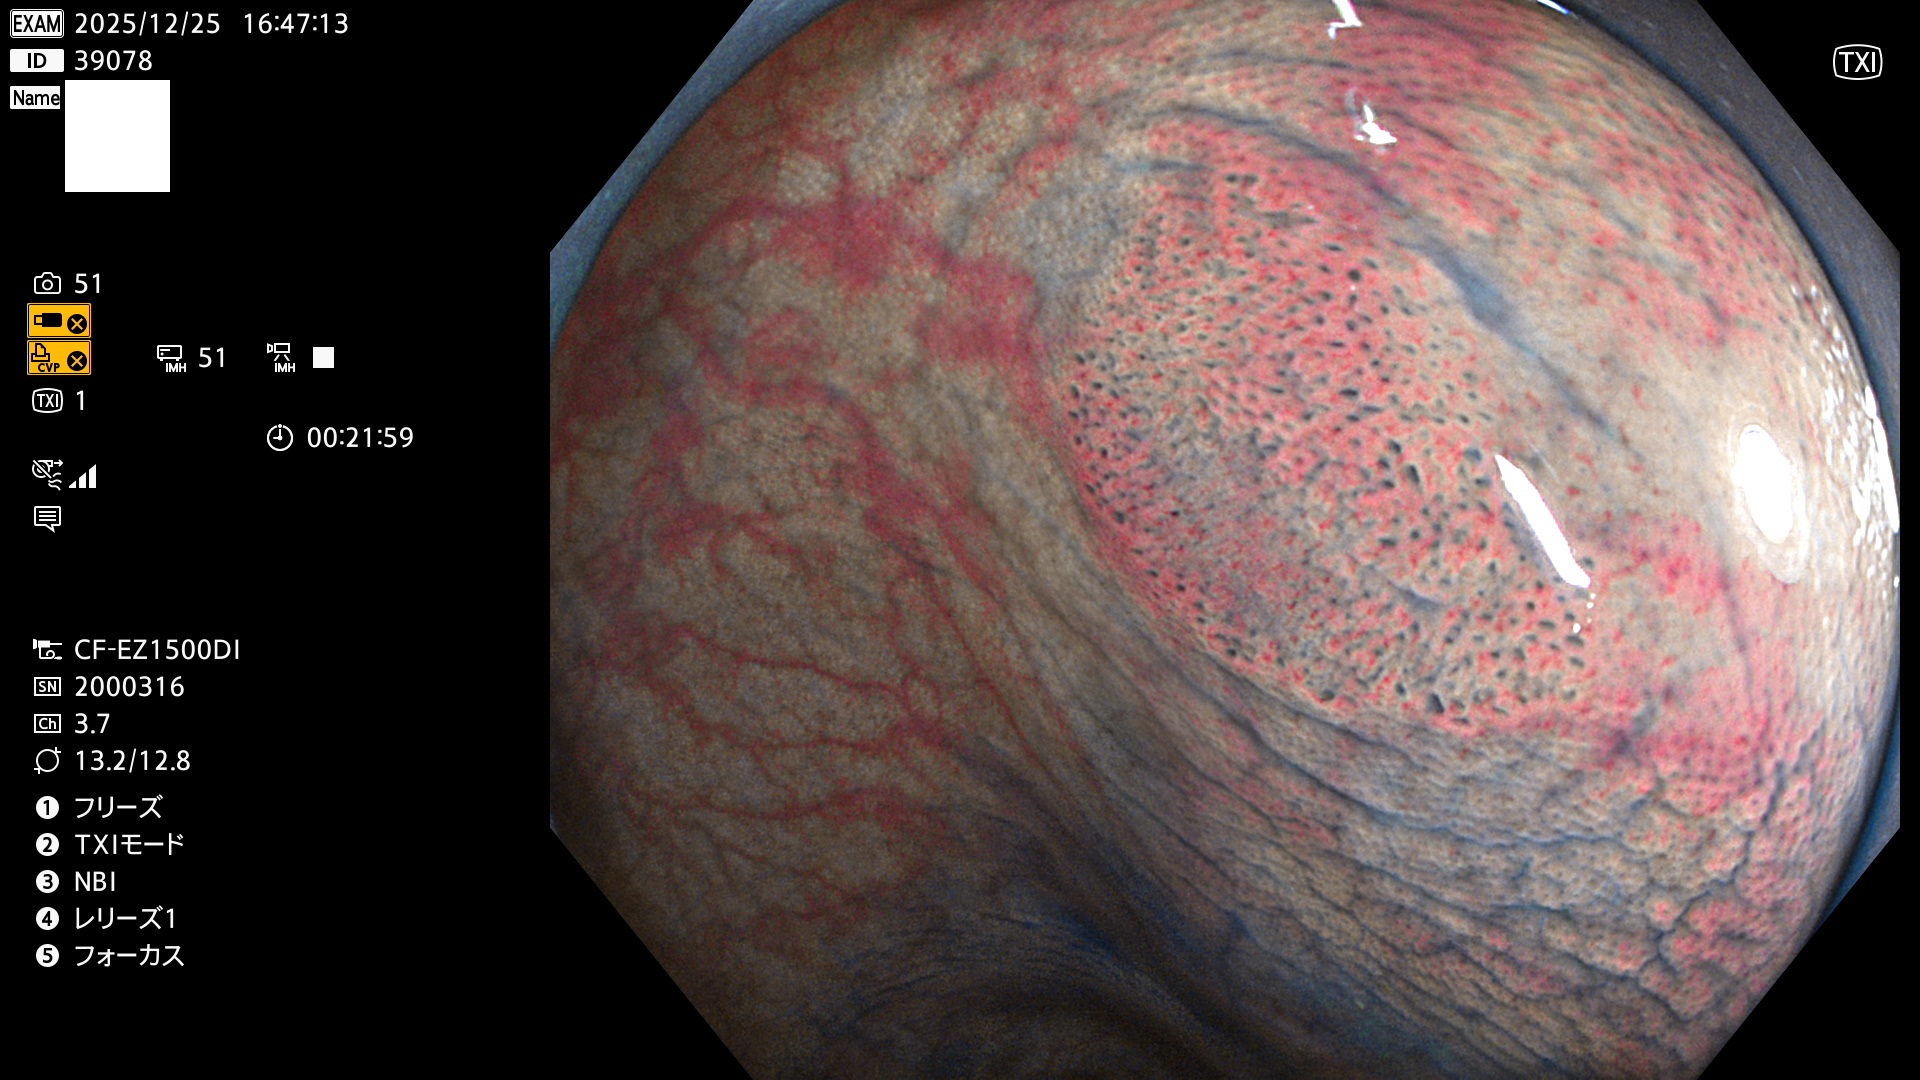

完全に平坦な物をUb、陥凹している物をUcと呼びます。Ubは認識が困難で、Ucはびらん(炎症)と紛らわしいために見落とされやすく、「内視鏡後・大腸癌」の原因になります。

専門的)何故、陥凹していると危険? 癌遺伝子の変異が蓄積すると細胞分裂が盛んになり隆起するのでは?と通常は思われるでしょう。しかし実際は逆です。これは2022年の記事にある「細胞はストレスに直面したら細胞分裂を止める(Dormancy 細胞老化に入り休眠する)という生命の基本的現象」によるものです(Oncogene Stress)。細胞老化を起こすのが癌抑制遺伝子で、この安全装置(ブレーキ)が壊れると癌になります(休眠からの覚醒)。ですから陥凹は「まだ癌では無いが癌化の直前」を意味します。特に「小サイズなのに陥凹している」病変は短期間に腫瘍進化(IntraTumor Heterogenity⇒2021年記事)が起きたことを意味します(=ゲノム不安定性)。

毎週の検査(木・金・土・日)に発見されたUbとUc型・腺腫を、その週の日曜の夜にUPし1週間、提示します。

2025年12月18日〜12月29日の8日間(80件)13個 (Uc_ADR=13個/80人=16%)